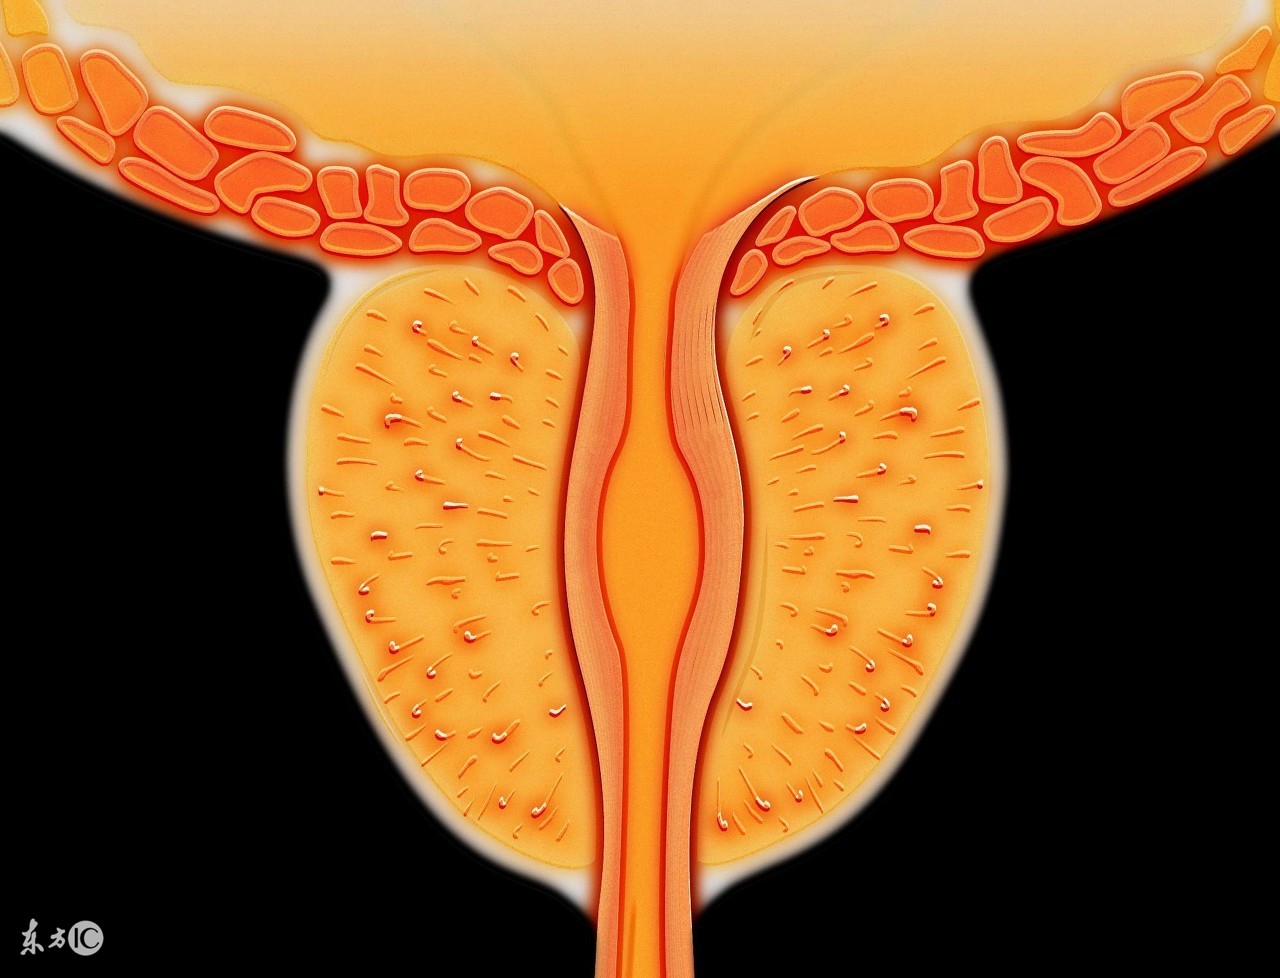

防治 膀胱破裂如为*力暴**所致, 应先处理威胁生命的损伤;医源性膀胱损伤应注重预防, 盆腔手术前常规留置导尿, 使膀胱处于非充盈状态;腔内手术时膀胱不宜过度充盈;膀胱肿瘤电切时注意控制深度, 在有闭孔神经反射时, 尽量使膀胱处于非充盈状态。前列腺电切时最好使用能连续灌洗的套鞘, 否则应及时放液, 液压灌注泵行术中冲洗为快进慢出, 应放弃使用。腹膜内型膀胱破裂大多主张手术治疗, 手术方式有膀胱裂口修补加造瘘术、膀胱单纯修补, 近年来有腹腔镜下修补腹膜内膀胱破裂成功报道[ 3] 。手术原则为清除腹腔内渗液及损伤组织、可吸收线缝合、膀胱周围间隙引流。腹膜内型膀胱破裂的非手术治疗报道相对较少, 主要包括:(1)半卧位, 留置尿管, 持续引流膀胱;(2)使用抗生素;(3)适度尿道牵引, 使导尿管位于膀胱低位, 导尿管盲端不致由裂口进入腹腔, 同时膀胱顶部或后壁裂口因膀胱颈向下牵引而易于闭合;(4)如有腹腔积液, 则行穿刺引流。腹腔大量无菌积液, 经留置静脉针引流出无色澄清液1000 ~ 1500ml ;(5)密切观察有无持续出血和血块阻塞导尿管情况, 作低压膀胱持续冲洗。作者认为若膀胱裂口小、逼尿肌收缩、裂口周缘水肿、裂口处血块形成等可使膀胱裂口在膀胱空虚时自行愈合, 可行保守治疗。严格掌握保守治疗的适应证十分关键, 作者按以下标准选择:(1)早期发现的单纯膀胱损伤;(2)症状体征较轻, 血流动力学稳定, 没有弥漫性腹膜炎或持续血尿表现;(3)B 超见少量腹腔积液、膀胱造影仅见少量或无尿外渗(但内腔镜操作并发膀胱破裂导致腹腔积液系无菌性, 可以不受腹腔积液量限制);(4)能放置导尿管, 保证膀胱内引流通畅。